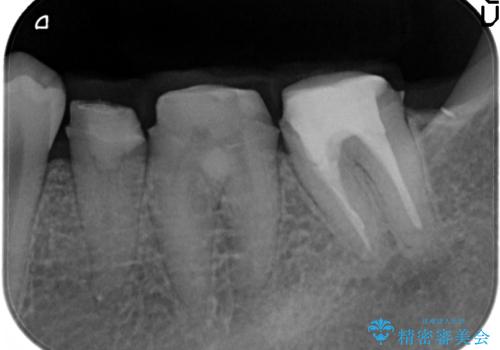

虫歯を除去すると、歯ぐきよりも深い虫歯であることが判明したため歯周外科を行い問題を解決していきます。

歯ぐきの炎症は虫歯や歯周病の再発原因となるため歯周外科による解決が望ましいです。